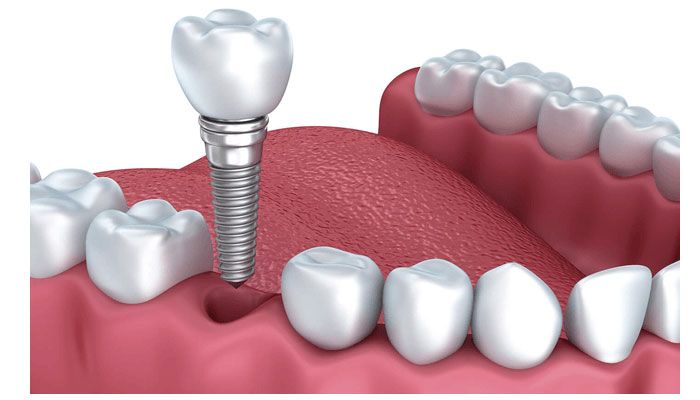

- Để răng Implant bám chặt, xương hàm phải đủ khối lượng và chất lượng. Nếu xương hàm không đủ, có thể cần thực hiện thêm phẫu thuật nâng xương hoặc cấy xương.

Hạn chế tình trạng tiêu xương

Răng khi bị mất, các bác sĩ luôn khuyên nên phục hồi ngay bằng phương pháp cấy trực tiếp trụ Implant vào xương hàm để tránh tình trạng tiêu xương. Nguyên nhân vì răng khi bị mất sẽ tạo khoảng trống trên hàm. Khoảng trống răng không còn chức năng ăn nhai. Vì thế theo cơ chế đào thải của cơ thể vùng xương sẽ bị tiêu. Tiêu xương khiến xương hàm biến dạng, da nhăn cũng như dễ gây rối loạn khớp cắn. Không chỉ gây mất thẩm mỹ mà còn gây tốn kém về sau khi phục hình.